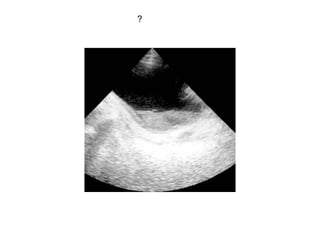

?